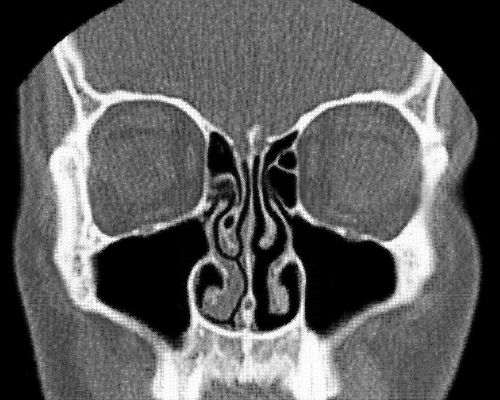

第一个告诉我人类拥有两个鼻子的论点是由罗纳德·埃克尔斯(Ronald Eccles)提出的,他是威尔士卡迪夫大学(Cardiff University)感冒研究中心的鼻腔专家,直到几年前退休。我知道这听起来很荒谬,但请考虑一下你的鼻子,或者说你的两个鼻子在内部是什么样子:每个鼻孔通向自己的鼻腔,不直接与另一个鼻孔相连接。它们是两个独立的器官,就像你的两只眼睛或两只耳朵一样。

鼻子远非被动的通道,它隐藏着不断变化的内部结构。正如埃克尔斯所说,鼻子内部有静脉勃起组织,其结构“与阴茎的勃起组织相似”,并且会充血。感染或过敏会加剧肿胀,以至于鼻腔会完全堵塞。

在健康的鼻子中,鼻腔组织的肿胀和消肿通常遵循一个称为“鼻周期”(Nasal cycle)的可预测模式。每隔几个小时,一侧的鼻子会部分充血,而另一侧会打开。随后它们交替进行,来回往复。